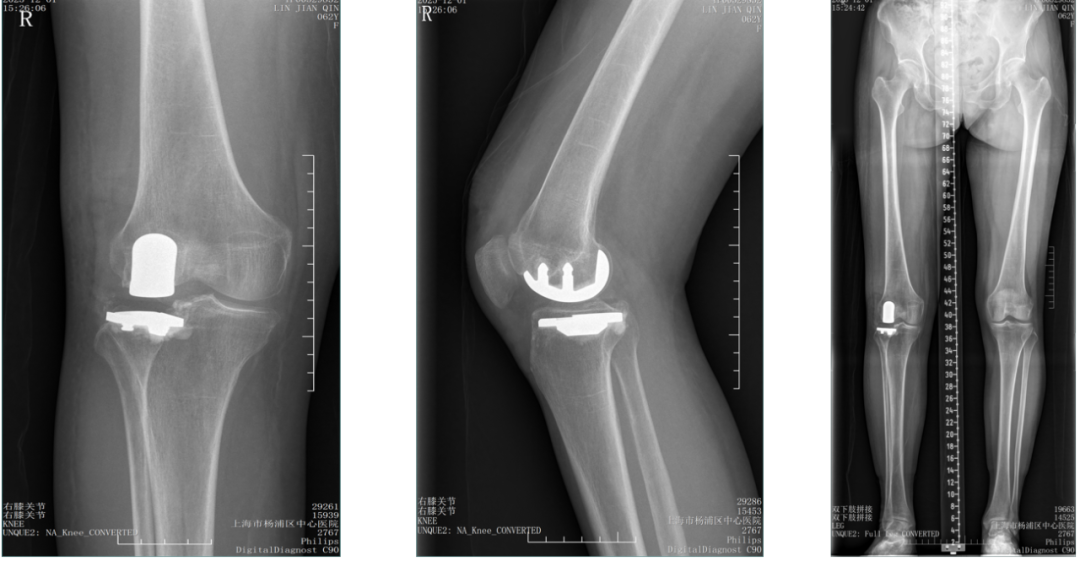

三、胫骨假体下沉翻修

外侧间室OA行LUKA,术后外伤导致胫骨假体塌陷

胫骨假体翻修术(保留股骨假体)

四、胫骨假体过度前倾翻修

LUKA术后胫骨假体过度前倾导致膝关节伸直受限

LUKA术后半年 (20251126)

保留股骨假体胫骨侧翻修

翻修术后 (20251201)